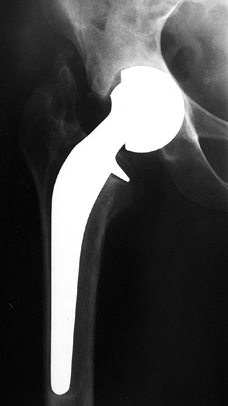

bearing for 2 months and then advance to a cane until union is visible

on radiographs (Fig. 125.21), usually 4–6 months after the procedure.

![]() |

|

Figure 125.21. Radiographs of a hip that underwent a varus osteotomy for osteonecrosis. A: Preoperative status. B: Six months after osteotomy. C: Ten years after surgery. The hip continues to function satisfactorily, although degenerative changes were eventually present.